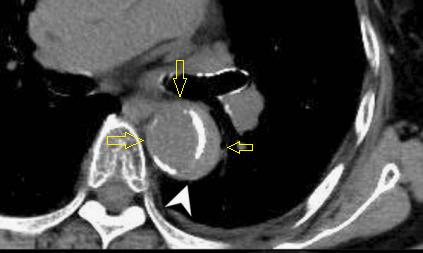

下图的胸部CT平扫,有什么大问题?

图4

仔细一看,主动脉里面有线样高密度阴影!这个要高度警惕主动脉夹层!

图5

增强CT一看,吓到一大片!太惊悚了!

图6